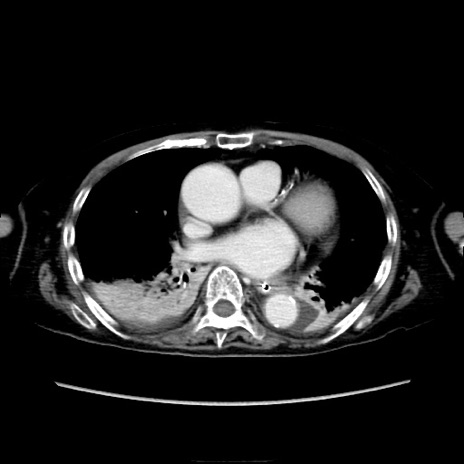

冠状断像